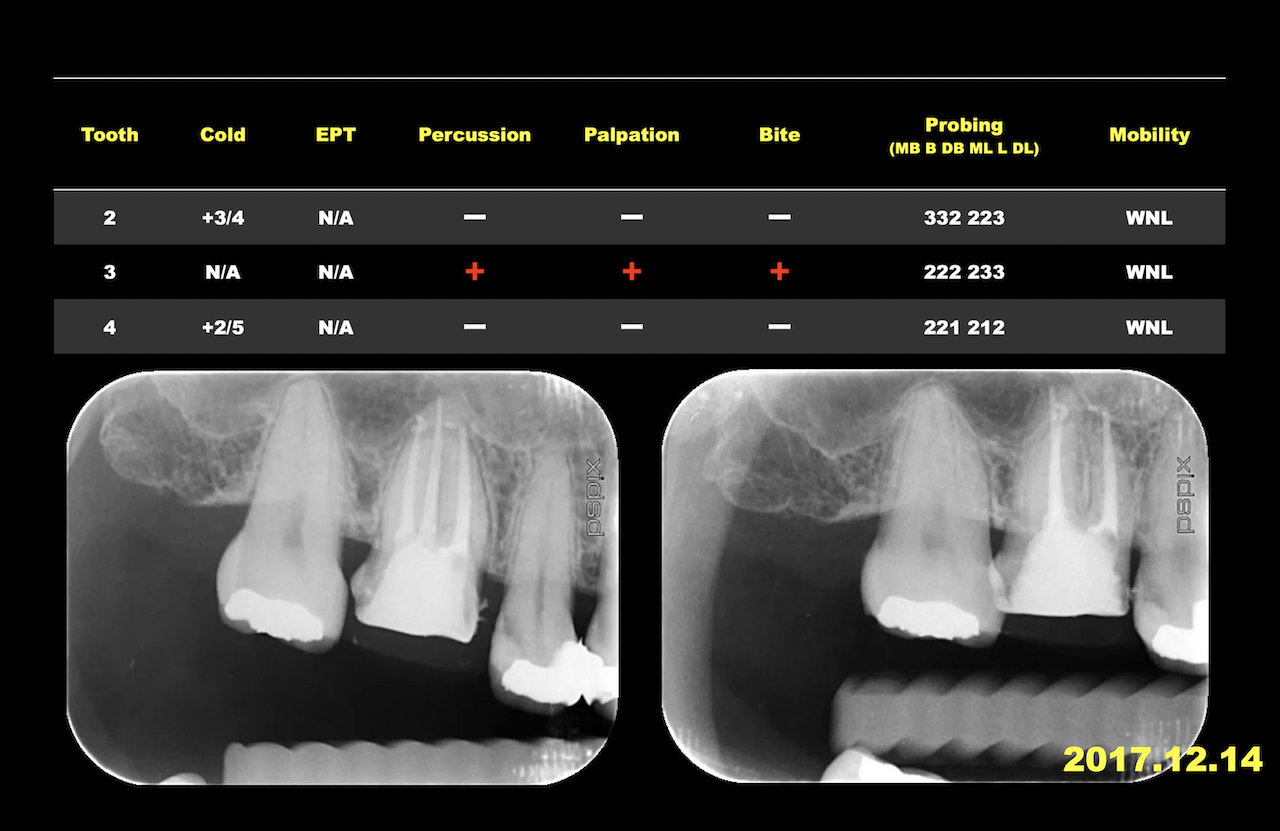

そして午後から診査・診断である。

文献的には以下の順が望ましいと言われているが、その実際を解説した。

そしてこの検査の実際を、Live形式で、この日の参加のインストラクターの先生に手伝っていただき、実際に当歯科医院で私が行っている方法で行った。

それはUSCで使用している診断の紙を用いてそれに基づいて行った。